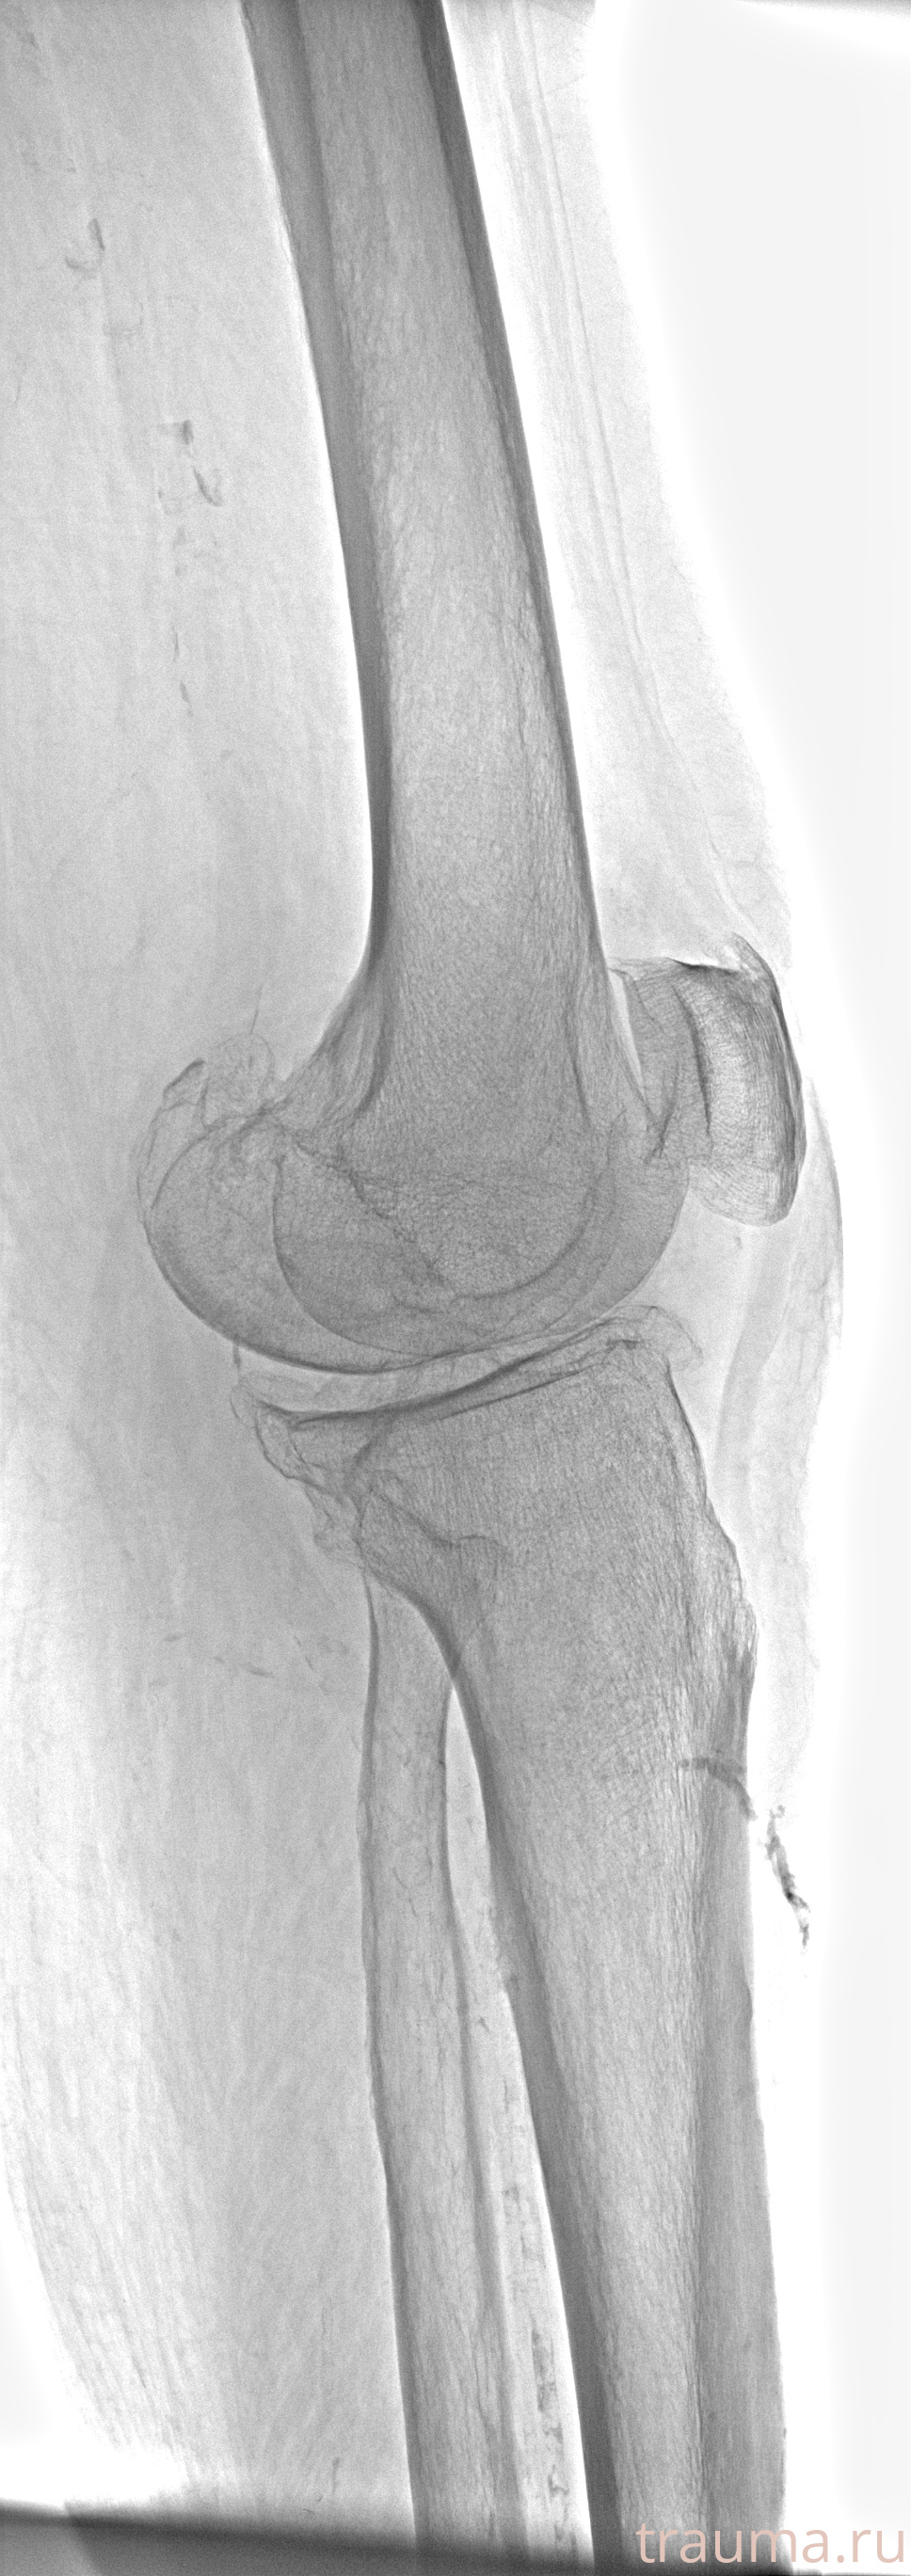

Рентгенограммы

Рентген на дому: по вашему адресу приезжает врач-рентгенолог, травматолог-ортопед с мобильным рентгеновским аппаратом, проводит диагностику травмы или заболевания, делает необходимые рентгенограммы, дает рекомендации по дальнейшему лечению. Получить качественные снимки в домашних условиях возможно благодаря уникальной методике, разработанной МосРентген Центром для института  Склифосовского